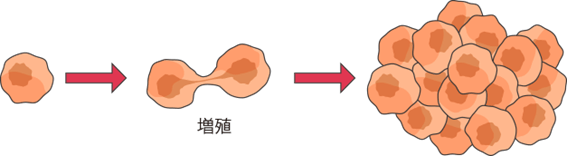

何らかの原因によって遺伝子に異常が起こり、そのことで限りなく増え続け(増殖)、別の場所に移動(転移)してしまう細胞を「がん細胞」といいます。がん細胞は増殖してまわりの臓器に影響を与え、また、身体のあちこちに転移して他の臓器にも影響を与えるようになります。

しかし、遺伝子が傷ついた異常な細胞の一部は、体からの命令を無視してどんどん増えたり、周りに広がったりする性質をもつようになります。これが、「がん細胞」です。がん細胞が何年もかけて増え続け、がんとして発見されると考えられています。

がんは、遺伝子が傷ついた異常な細胞(がん細胞)がかたまってできたものです。がん細胞は、増え続けかたまりを作る性質をもっています。

また、がん細胞は、増え続けるだけでなく、周囲に広がったり(浸潤)、他の臓器に移ったり(転移)して新しいがんを作る特徴があります。